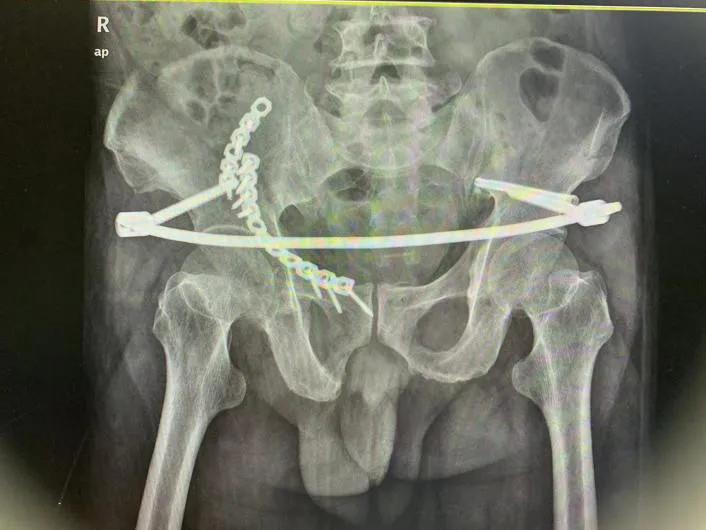

术后影像资料

拆除内固定后影像资料